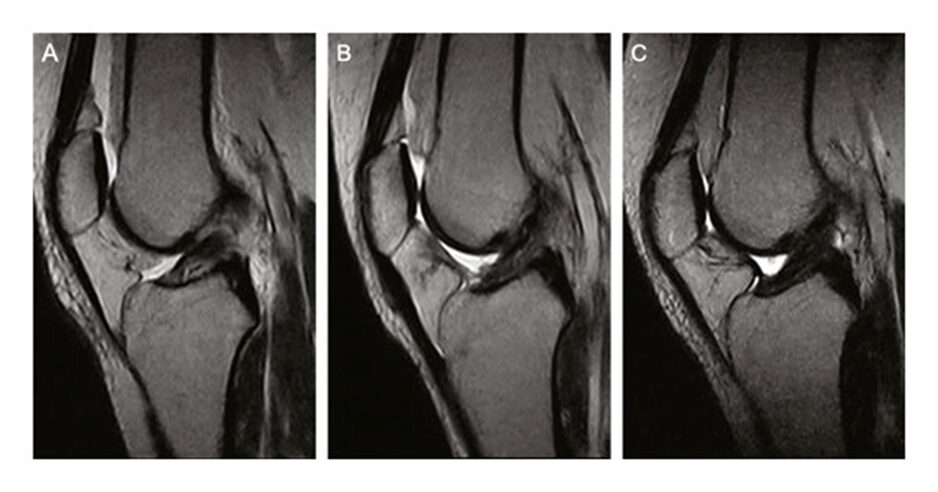

In solchen Fällen zeigt sich im MRT ein neu aufgebautes, belastbares Kreuzband.

In meiner Praxis zeigen sich in vielen Fällen dokumentierte Verläufe, bei denen nach entsprechender Behandlung im MRT wieder ein belastbares Kreuzband nachweisbar ist.

In meiner Praxis liegen dokumentierte Verläufe vor, bei denen sich nach der Behandlung nicht nur eine funktionelle Stabilisierung, sondern auch eine im MRT nachweisbare strukturelle Wiederherstellung des Kreuzbandes gezeigt hat.